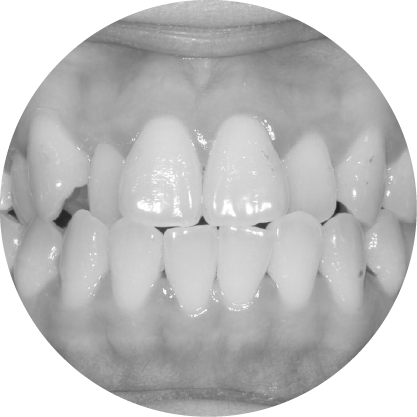

ตัวอย่างในชีวิตจริง